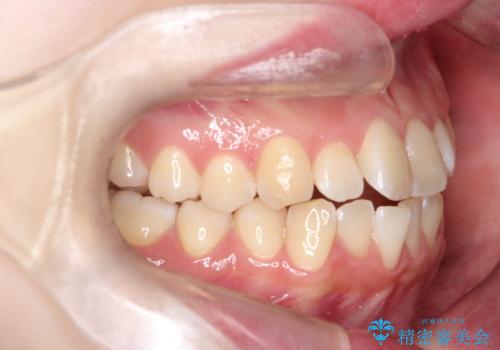

【インビザライン】オープンバイト。凸凹を治したい

- オープンバイトを主訴に来院されました。

インビザラインを用いIPRと遠心移動を行いオープンバイトと叢生の改善を行なっております。

前歯の叢生がわずかにありますが、追加アライナーの作成は希望されなかったため、歯を動かしていく動的治療は終了となりました。